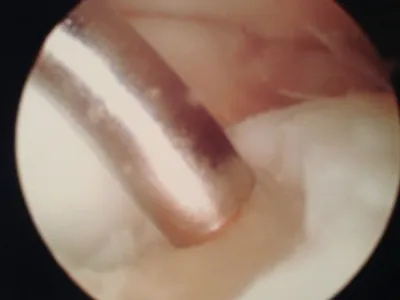

Intraop arthroscopic pics of talar OCD surgery.

A series of intraop ankle arthroscopy pics of synovial chondromatosis with OCD talus and tibia and microfracture.

Pic of one of the nodules inside the ankle joint.